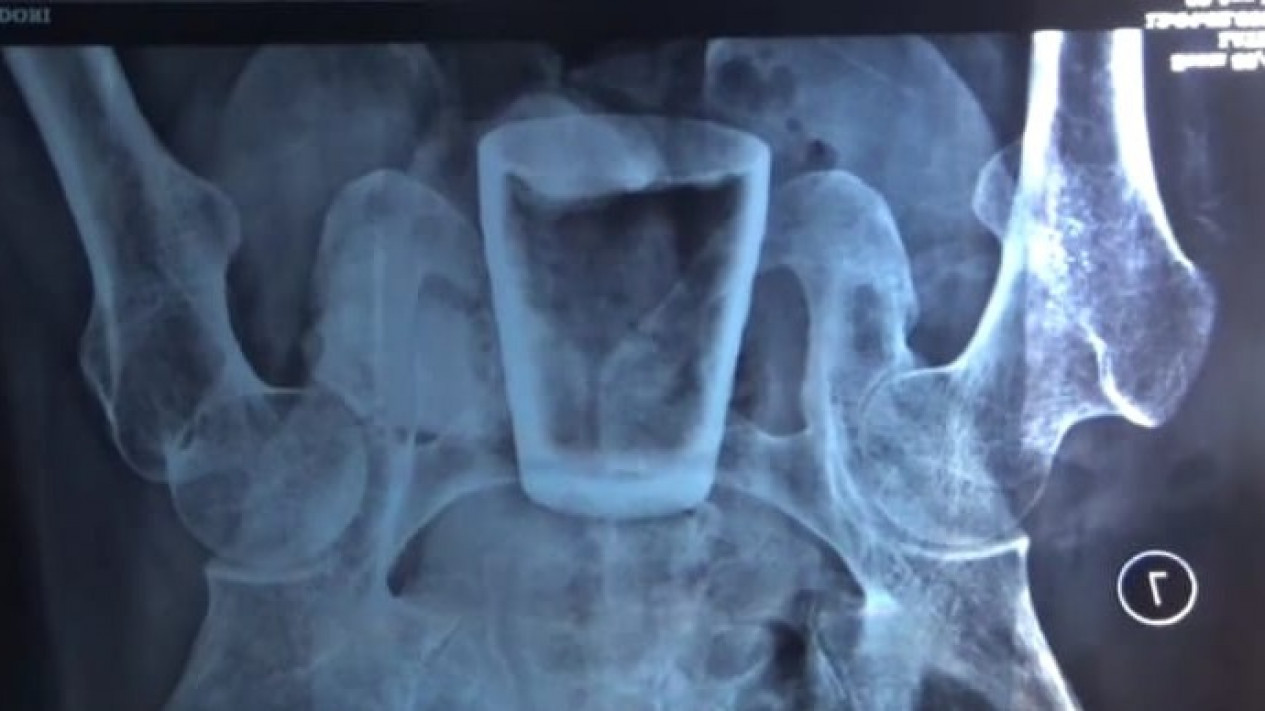

Hasil rontgen Lasidi yang memperlihatkan sebuah gelas di dalam perutnya.

Dan ternyata saat dirontgen, mereka melihat hal yang tidak masuk akal. Ada gelas kaca di dalam perut Lasiadi.

"Saya tidak tahu gimana, kok, ada gelas yang udah cuil masuk ke dalam perut saya. Padahal ukuran gelas tidak mungkin bisa ditelan manusia," tutur Lasiadi keheranan.